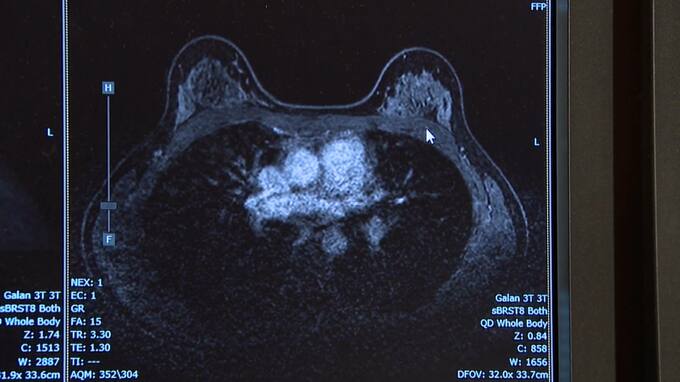

福岡県内でMRIによる乳がん検診を実施している医療機関を調べてみるとおおむね2万円~3万円程度。(福岡山王病院ではMRIによる乳がん検診は行っていません)

マンモグラフィーや超音波検査に比べると高額ですが、乳がん検診の新たな選択肢として導入する医療機関は徐々に増えています。